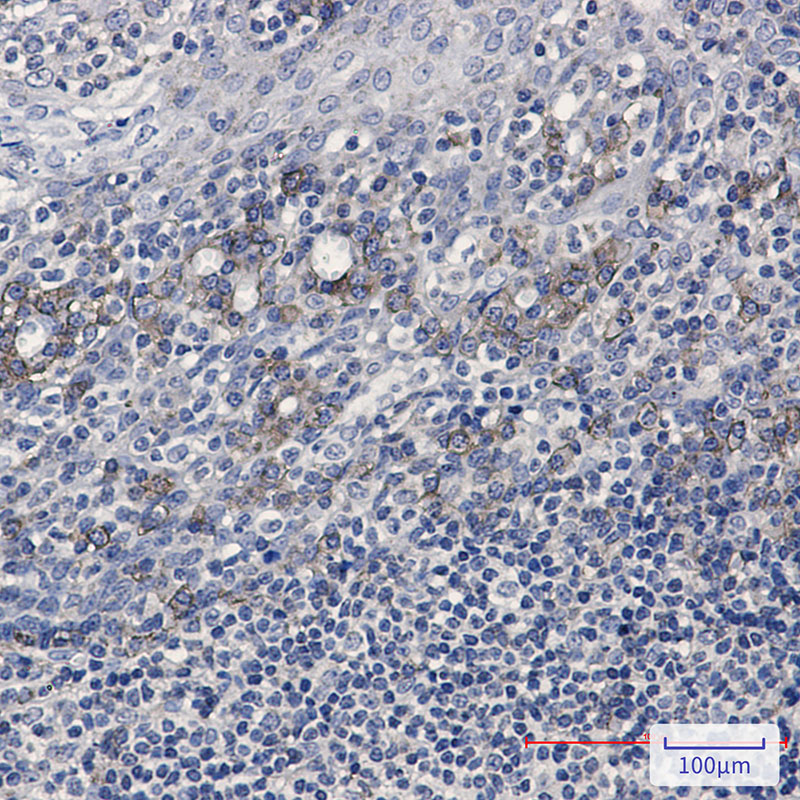

Immunohistochemistry analysis of paraffin-embedded Human tonsil using CD32B antibody.High-pressure and temperature Sodium Citrate pH 6.0 was used for antigen retrieval.